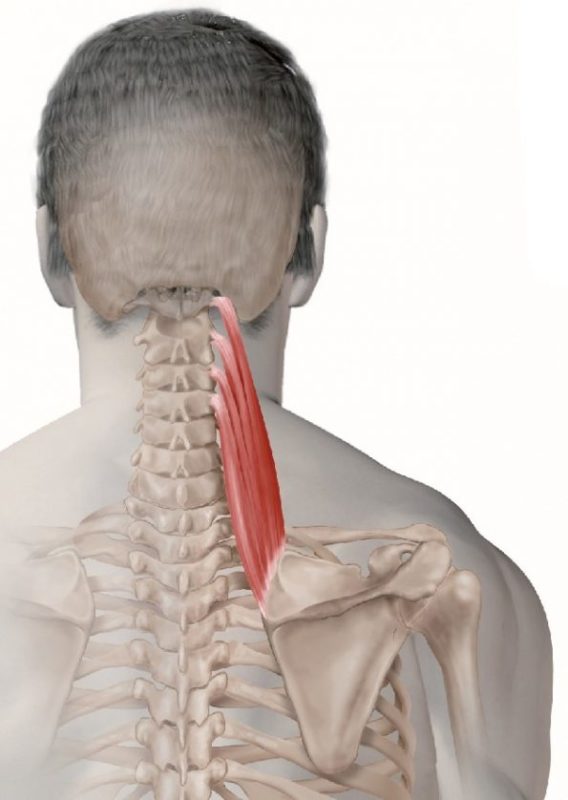

Questa coppia di muscoli si trova lungo la schiena e i lati del collo, viaggiando dalla colonna cervicale superiore fino alla scapola (scapola). La scapola levatrice svolge un ruolo chiave nel sollevare o elevare la scapola, oltre ad aiutare nei vari movimenti del collo. Se la scapola inizia a inclinarsi in avanti e a ruotare verso l’alto con spalle arrotondate, i muscoli scapole del levatore possono accorciarsi.